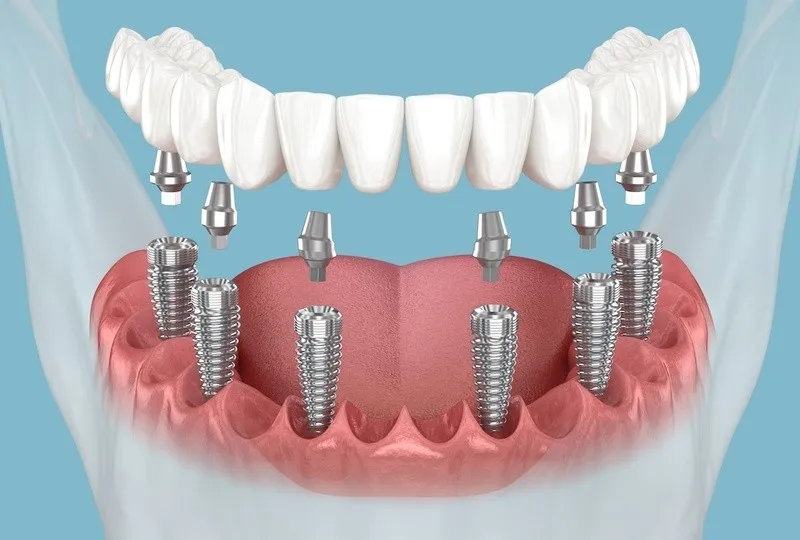

Kỹ thuật cấy ghép Implant phức tạp không chỉ đòi hỏi việc đặt trụ Implant mà còn bao gồm các thủ thuật tái tạo xương và mô